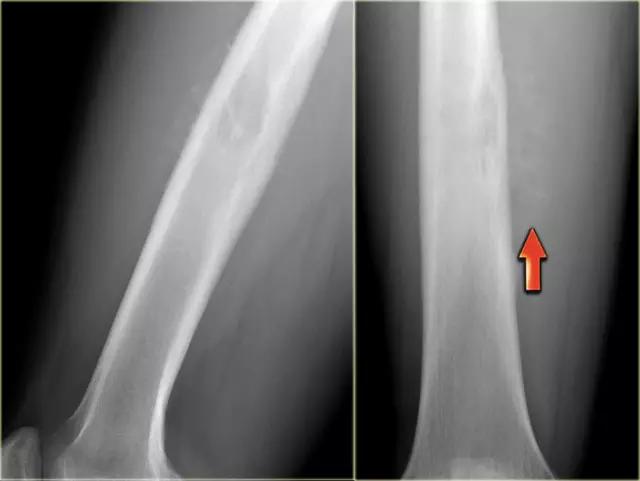

X-射线显示在腿的各个区域的典型损伤。(左)胫骨(胫骨)的病变。(中心)在膝盖附近的大腿骨(股骨)的两个损伤。(右)臀部附近的上大腿骨的大病变。